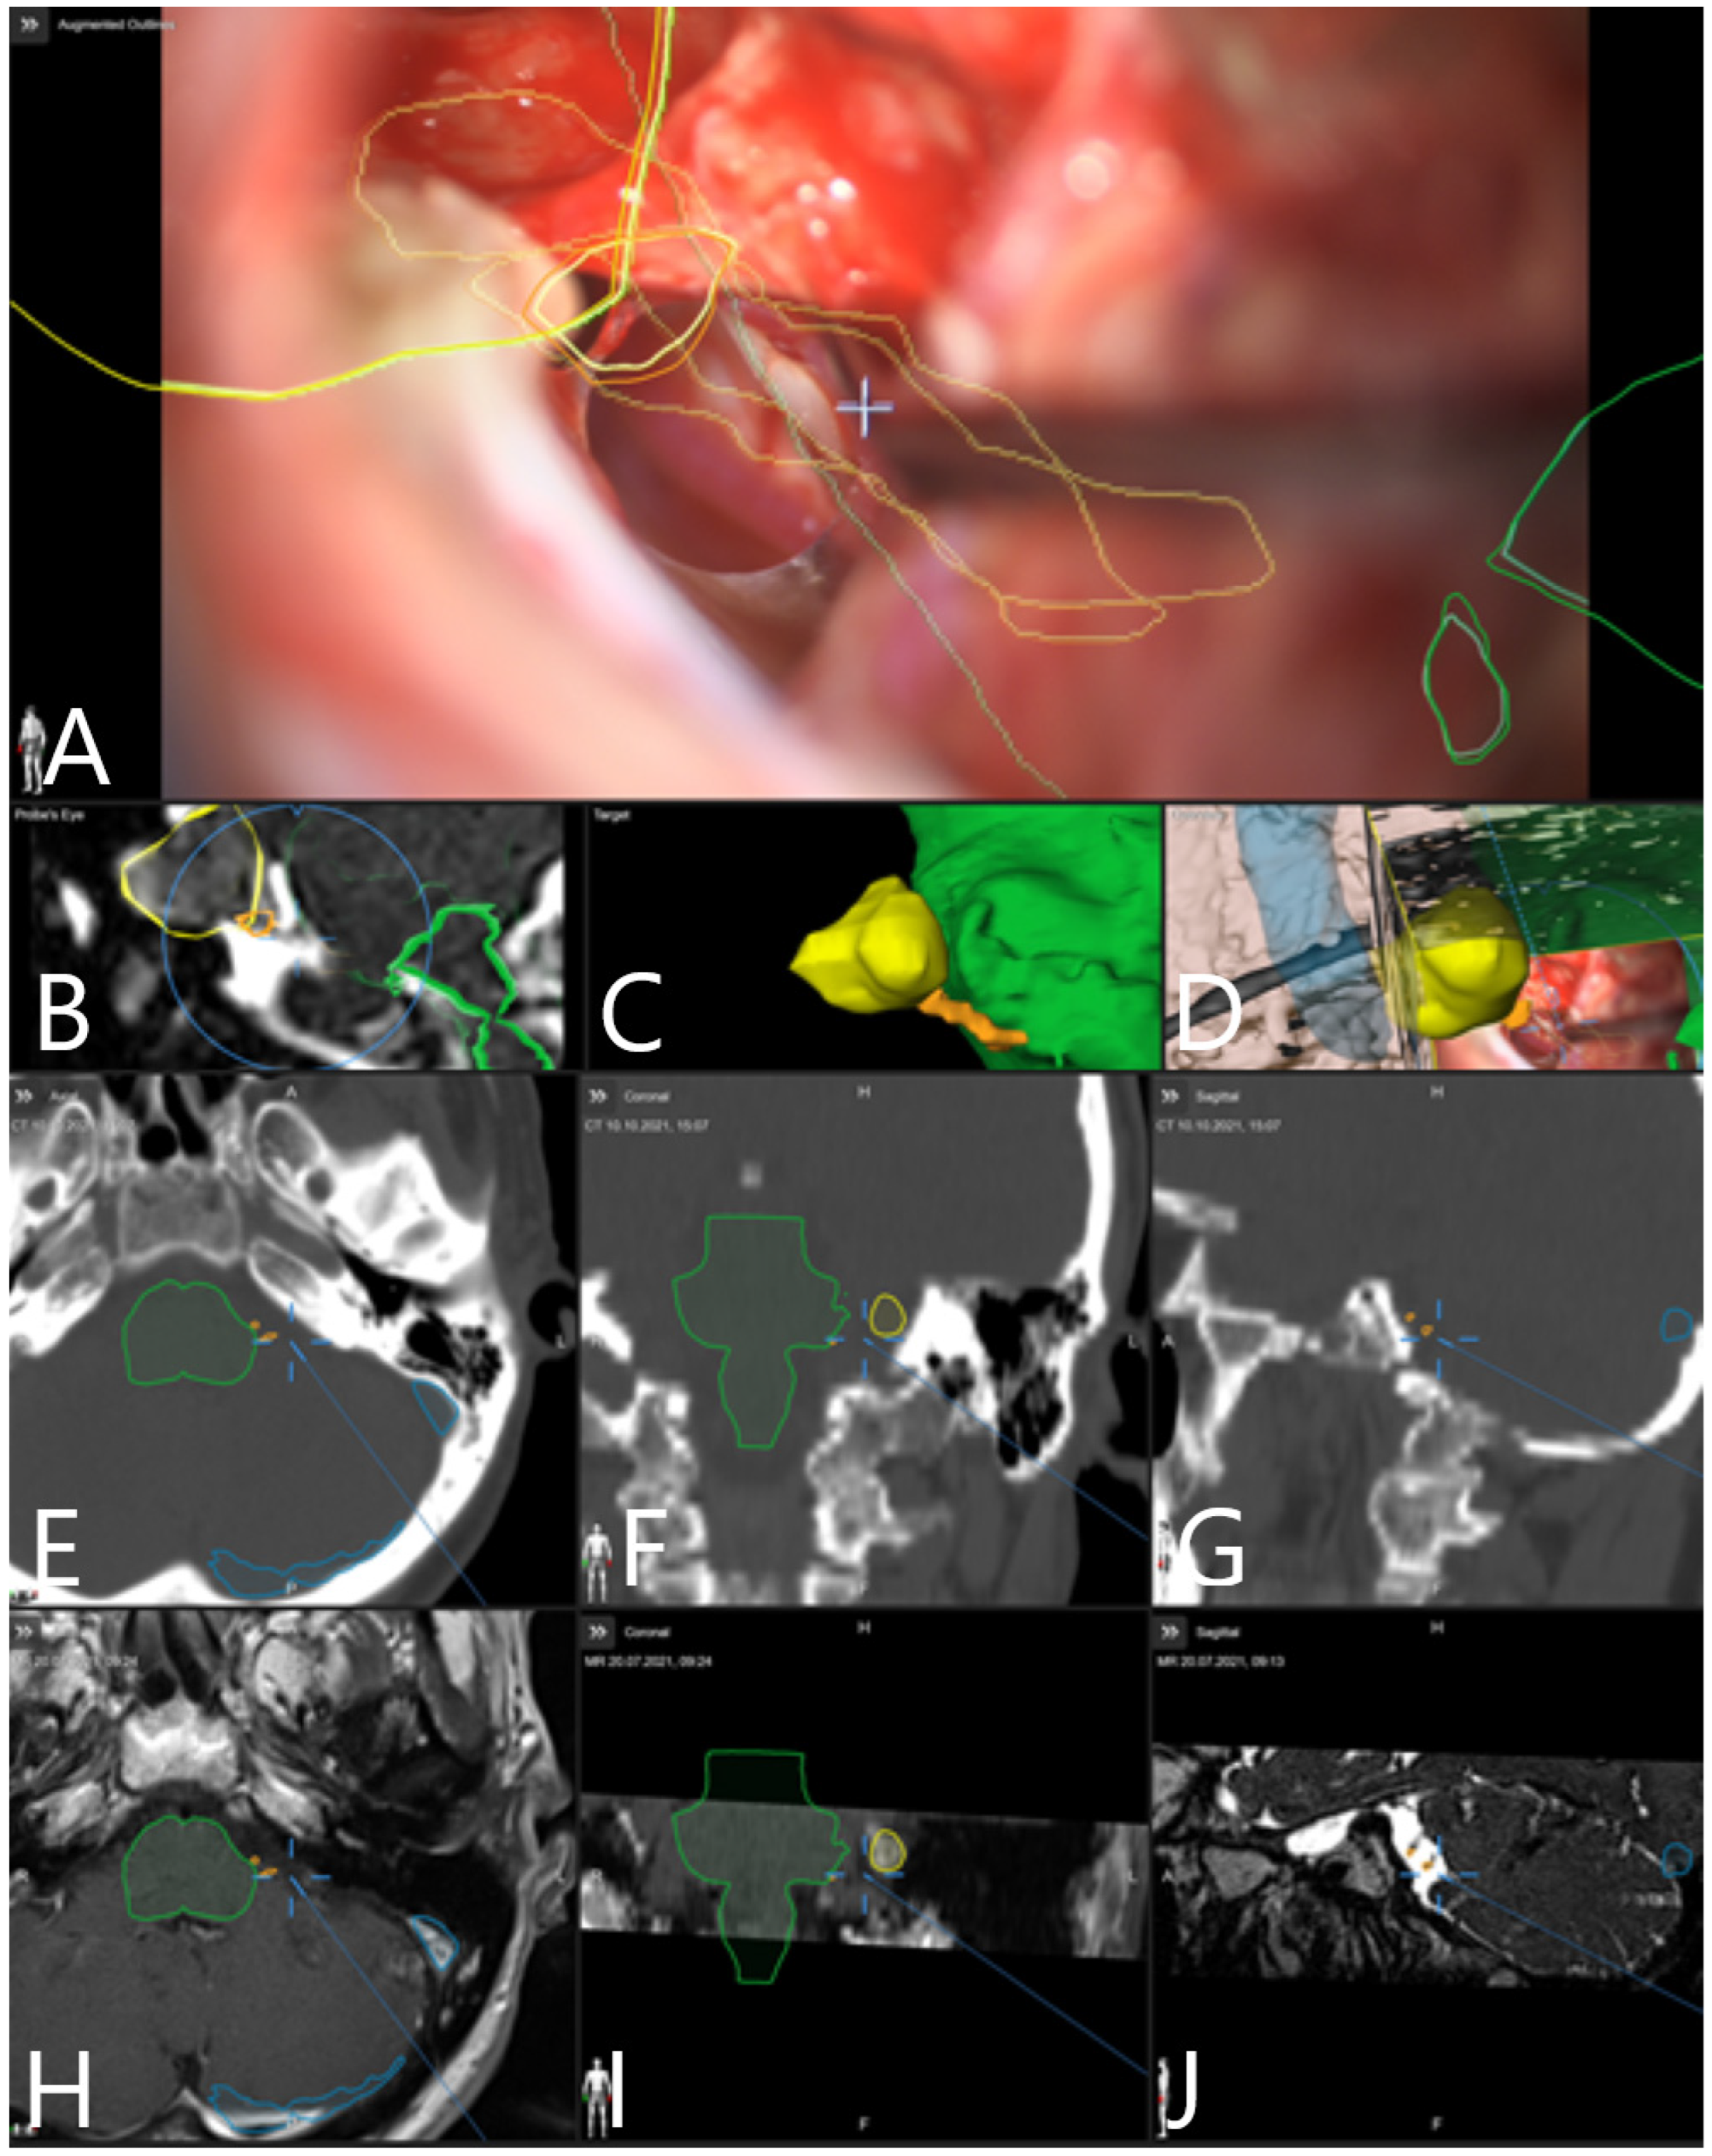

| Patient Number | Segmented Structures in AR Advantages: Craniotomy Planning, Dural Opening, Relations of Tumor to CN V, Localization of Origin of CVI and CVIII at the Brain Stem, Relations of Tumor to Brain Stem, Localization of IV Ventricle, Segmentation of Tumor Cyst, Localization of Structures of the Middle Ear for Facilitation of Drilling on Inner Acoustic Meatus, Relations of Tumor to Arterial Vessels and to Petrosal Vein | ||||||||||

|---|---|---|---|---|---|---|---|---|---|---|---|

| Sigmoid Sinus | Transverse Sinus | Tumor Outline | CN VII and VII Origin at Brain Stem | CN V | Petrous Vein | Arterial Vessels (AICA, PICA, SCA) | Brain Stem | Middle Ear, Cochlea and Semicircular Canals | Pyramidal Tract | IV Ventricle | |

| 28 | + | + | + | − | − | − | + | − | − | − | − |

| 29 | + | + | + | − | − | + | + | − | − | − | − |

| 30 | + | + | + | − | − | + | + | + | − | + | − |

| 31 | + | + | + | − | − | + | − | + | + | − | − |

| 32 | + | + | + | − | − | − | − | + | + | − | + |

| 33 | + | + | + | + | − | − | − | + | − | − | + |

| 34 | + | + | + | + | − | − | − | + | + | − | − |

| 35 | + | + | + | + | − | − | − | + | + | . | − |

| 36 | + | + | + | + | + | − | − | + | − | − | − |

| 37 | + | + | + | − | − | + | − | + | + | − | − |

| 38 | + | + | + | + | + | + | − | + | + | − | − |

| 39 | + | + | + | − | + | − | − | + | + | − | − |

| 40 | + | + | + | + | + | − | − | + | + | − | − |

| 41 | + | + | + | − | + | − | − | + | + | − | − |

| 42 | + | + | + | + | + | − | − | − | − | − | |

| 43 | + | + | + | + | + | + | − | + | + | − | − |